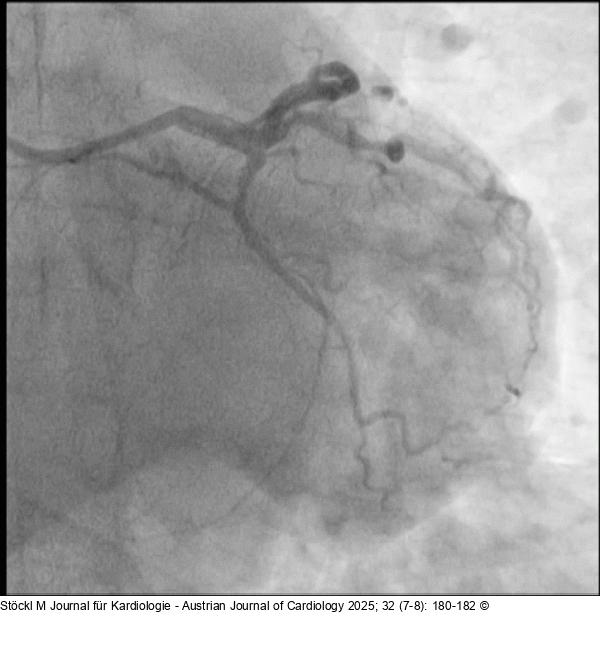

Abbildung 6: CX: Ballon CX: Ryurei 1,25/15 mm Ballon (Terumo) sowie NEON™ 2,0/20 mm Ballon, anschließend SELUTION SLR™ 2,0/20 mm DEBs |

CX: Ryurei 1,25/15 mm Ballon (Terumo) sowie NEON™ 2,0/20 mm Ballon, anschließend SELUTION SLR™ 2,0/20 mm DEBs |